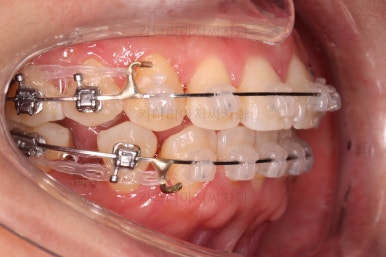

중앙선 개선을 위해 미니스크류와 다양한 장치를 활용해 주고요.

발치 공간도 많이 줄었네요.

중앙선, 교합 등을 더 신경쓰고 마무리를 합니다.

마무리 전에 부산교정치과 충치치료도 깔끔히 진행하게 됩니다.

위아래 좌우 치아가 없는 위치가 모두 달랐지만 교합도 잘 구성했고요.

아무래도 좌우 치아 크기들이 다르다 보니(뽑은 치아가 다르니) 중앙선은 100% 일직선은 안맞더라도 매우 정상 범주로 마무리를 할 수 있었습니다.

특히 어금니에 보이던 충치도 깔끔하게 마무리 했고요.